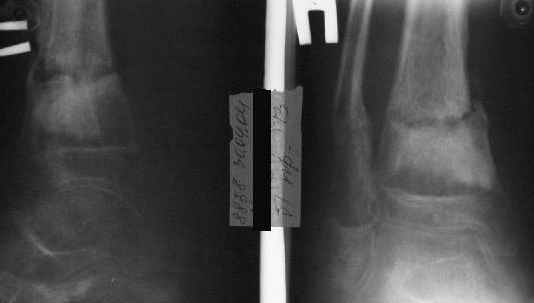

В январе 2005: варусная деформация н\3 голени, болевой с-м, комбинированная контрактура г\стопного сустава, нейропатия м\берцового нерва сохраняется слабость разгибания 1 пальца.

Оказытся... на снимках от 13.10.04 и 21.01.05 - больному 14 лет.

A> В январе 2005: варусная деформация н\3 голени,

Есть даже тень периостальной костной мозоли и сросшийся перелом

малоберцовой кости.

Это сросшийся перелом малоберцовой кости. И ложный сустав

н\3 б\берцовой кости.

Промежуточный

|